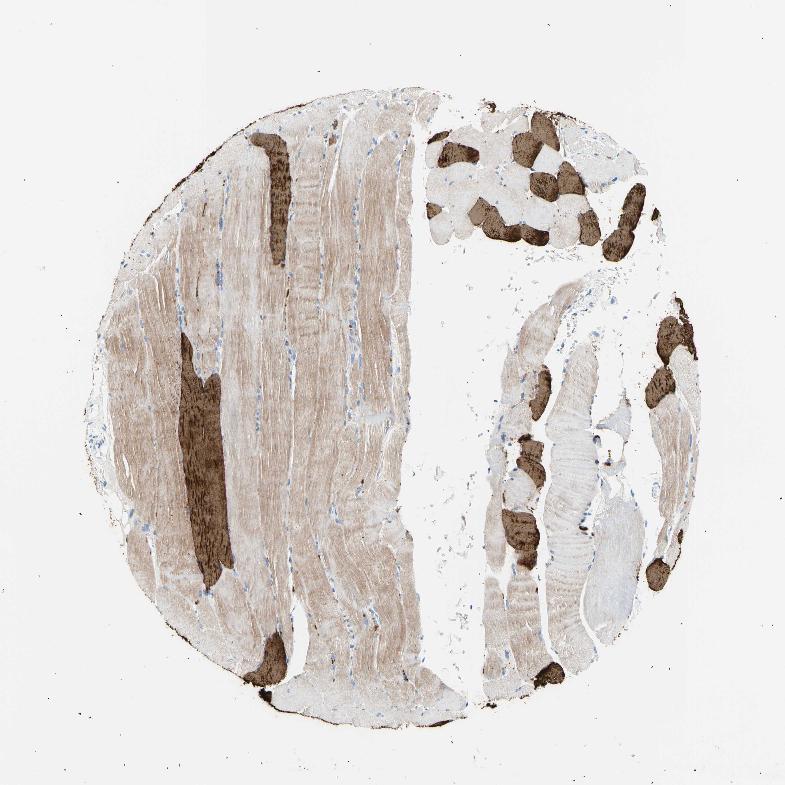

SKELETAL MUSCLE - Antibody stainingi

Antibody staining in the annotated cell types in the current human tissue is reported as not detected, low, medium, or high, based on conventional immunohistochemistry profiling in selected tissues. This score is based on the combination of the staining intensity and fraction of stained cells.

Each image is clickable and will lead to virtual microscopy that enables deeper exploration of all samples and also displays staining intensity scores, fraction scores and subcellular localization as well as patient and tissue information for each sample.

Antibody HPA001349Antibody CAB010760

Myocytes MediumHigh